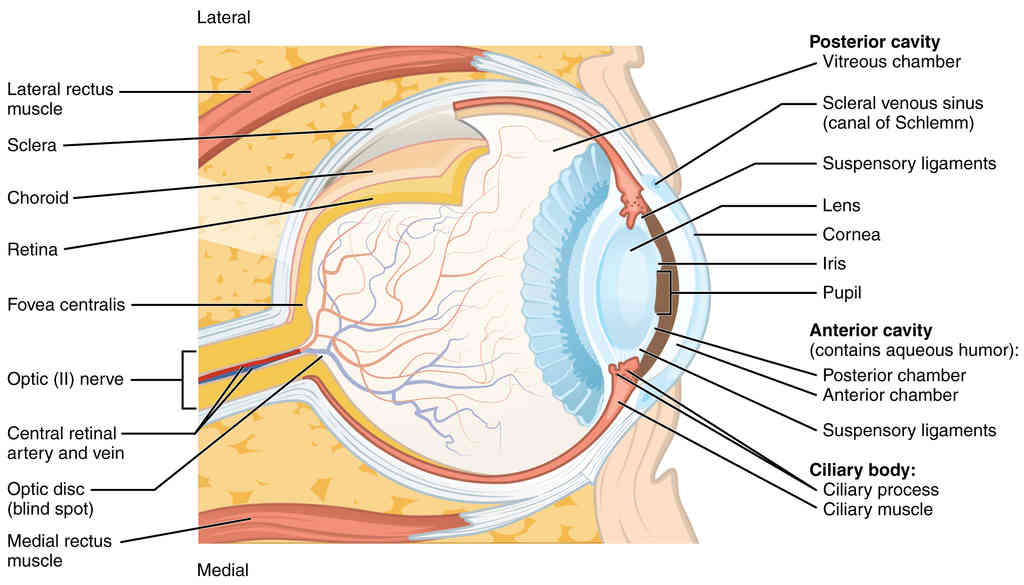

This page is under construction. For now, it is just a resource of the images found in the OpenStax Anatomy and Physiology Handbook. It wil slowly change into a revision tool. Each slide has a number. Use this to refer to the slide. When completed, it will have an unlabelled section, with labelled slides in parallel. On the unlabelled slides, write your answer and use the labelled slide to assess yourself. Keep track by also noting the number on each slide. Improvement at each attempt is important, more so than full marks on a first attempt.